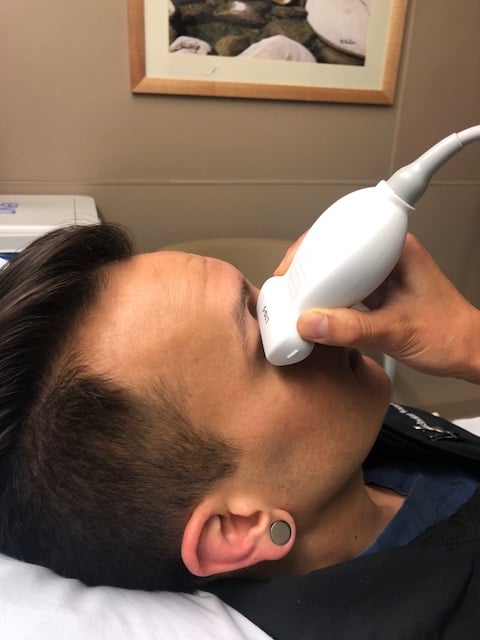

- Figure 2. A high-resolution linear array ultrasound transducer is being applied to the closed eyelid to perform an ocular examination.

- The linear array transducer is the most appropriate for performing ocular ultrasound because of the higher frequency and resolution. Endocavitary probe can also be used in place of a linear array probe as it is high frequency as well.

- Lie the patient supine or partially upright position and ask them to close their eyes.

- Put copious amounts of gel on the patient’s closed eyelid(s).

- Gently place the transducer in transverse plane on top of the gel, making no direct contact with the eyelid and applying no pressure onto the eyelid.

- Steady your hand with your fifth digit on the patient’s nose or temple.

- The ocular structures are to be evaluated in the neutral position while the patient performs gentle eye movements from side to side and up and down.